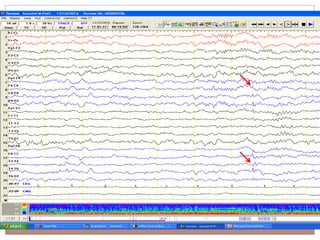

SREDA

Subclinical Rhythmic Electrographic Discharge Of Adults